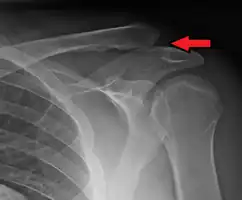

Type 3

Type 3 AC joint separation on plain X ray

This is a more severe form of a type III injury, with the trapezial and deltoid fascia stripped off of the acromion as well as the clavicle. This is type III but with exaggeration of the vertical displacement of the clavicle from the scapula. Distinguishing between Type III and Type V separations based on radiographs is difficult and often unreliable between surgeons.[19] Type V is manifested by a 2- to 3-fold increase in the coracoclavicular distance.[13] The shoulder manifests as a severe droop, secondary to downward displacement of the scapula and humerus due to loss of the clavicular strut.[13]